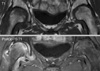

Fig. 3

Serial radiographs taken during follow-up. (A) Anteroposterior radiograph obtained at 4 weeks postpartum shows marked osteopenia in both proximal femurs. The bone density in the left side had increased and that in the right side had decreased slightly as compared with radiographs taken at 1 week postpartum (Fig. 1). (B) Anteroposterior radiograph obtained at 7 weeks postpartum shows increased osteopenia in the right femoral head. However, bone density in the left femoral head had recovered markedly. At this time, the left hip pain had almost completely disappeared. (C) Anteroposterior radiograph obtained at 11 weeks postpartum shows markedly increased bone density in both femoral heads. At this time, the right hip pain had almost completely disappeared. (D) Anteroposterior radiograph obtained at 20 weeks postpartum shows complete bone density recovery in both femoral heads. Slight dimpling (arrow) is observed in the superolateral end of the right femoral head, and this was persistent on anteroposterior radiograph taken at one year postpartum.

Fig. 4

On MR images taken at 7 weeks postpartum, the bone marrow edema in the left proximal femur had decreased markedly, whereas bone marrow edema persists in the right proximal femur. At this time, left hip pain had almost completely disappeared.